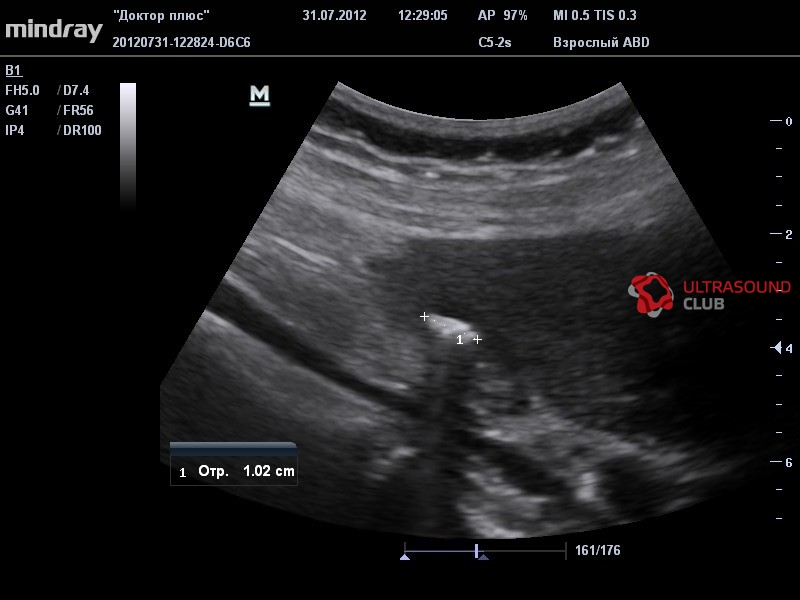

- Конвексный датчик С5-2s, 1,5 - 5,6 МГц(2.5, 3.5, 5.0, H5.0, H6.0), рад. кривизны 51 мм, 128 элементов